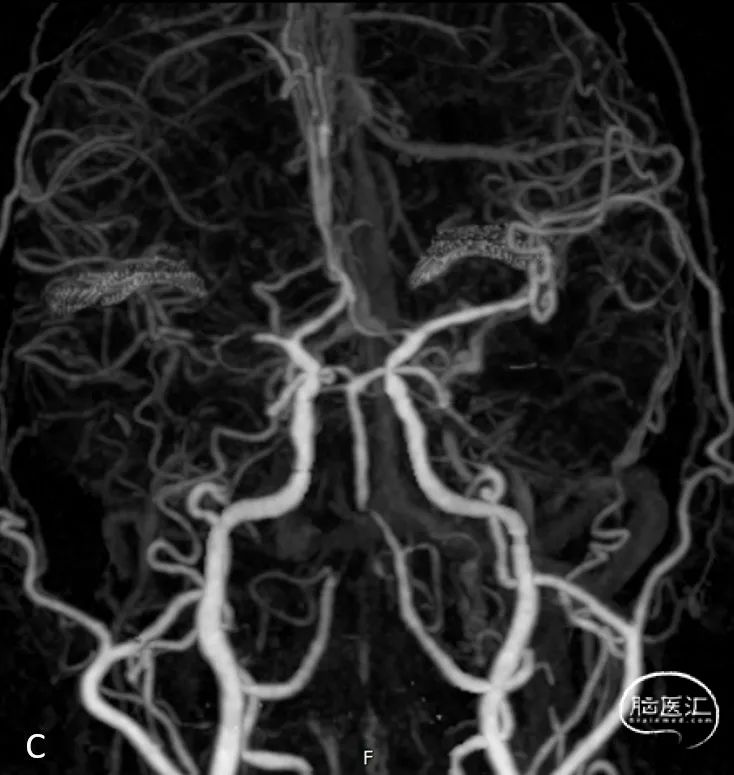

头颅CTA提示:右侧大脑中动脉M1段闭塞;左侧椎动脉V4段重度狭窄(C、D)

脑血管造影:右侧大脑中动脉M1段闭塞,代偿不足。

左椎动脉V4段重度狭窄。